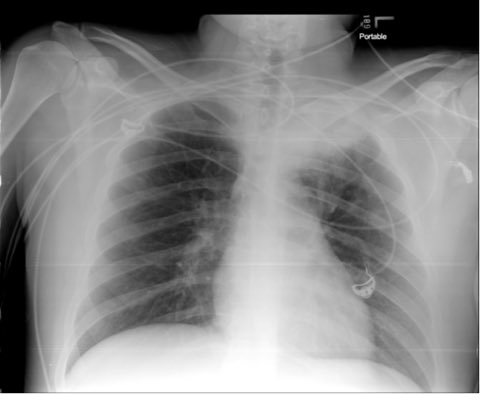

CXR below

11/ Chest CT below